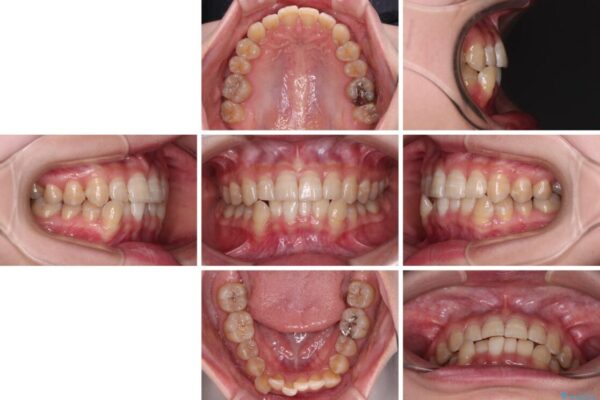

下顎の八重歯を気にして来院された患者様です。

下顎前歯にデコボコが集中していたため、顎間ゴムによる後方移動とIPR(歯と歯の間を削ること)により歯列を整えることとしました。

治療前、下顎前歯のデコボコが集中しており、奥歯の咬み合わせは、上顎に対して下顎が前方位にある状態でした。下顎の歯列を後方へ移動させる治療はインビザラインの得意とするところですので、1年程度で無事に治療を終えることができました。

治療前

• 【モニター】下顎前歯のデコボコをインビザラインできれいに 治療前画像